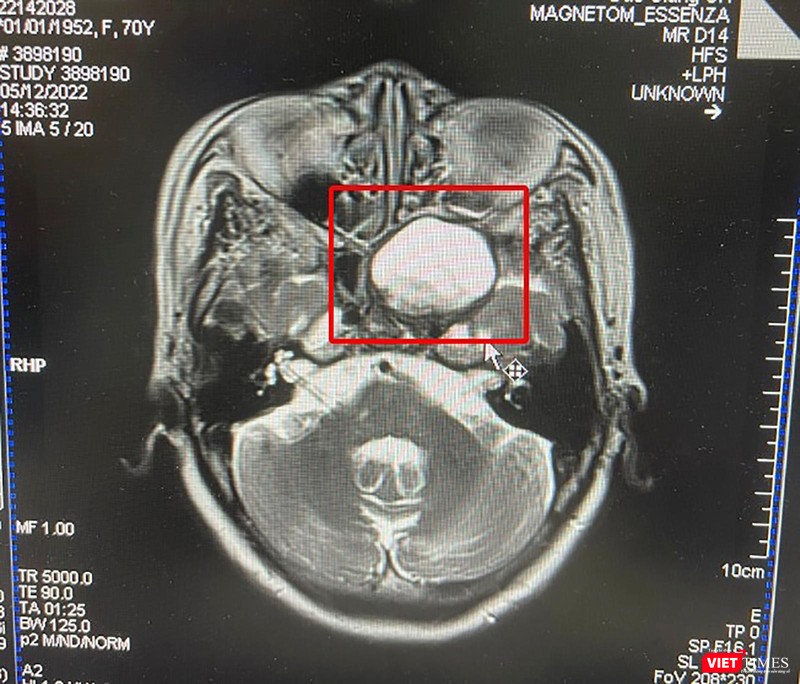

Qua chẩn đoán hình ảnh, khối u được xác định có kích thước lớn 32x32x38 mm (bằng quả trứng gà), lấp đầy thành xoang bướm xâm lấn nội soi chèn ép hố yên. Hội chẩn liên khoa, bệnh nhân được chỉ định phẫu thuật lấy u nhầy để tránh tình trạng u lớn chèn ép hốc mắt nhiều hơn, gây suy giảm thị lực, chèn ép nội sọ gây nguy hiểm tới tính mạng.

Phim chụp khối u nhầy xoang bướm ở bệnh nhân |

"Nguyên nhân gây u nhầy xoang bướm hiện chưa được xác định, ở trường hợp bệnh nhân này: tiền sử viêm xoang bướm nhưng bệnh nhân chủ quan không kiểm tra nên để khối u phát triển quá to kích thước 3,2x3,2x3,8cm, bên trong lòng xoang lại có tổ chức nấm và mủ nên triệu chứng đau đầu, nôn rầm rộ của bệnh nhân là khá điển hình. Khó khăn của ca mổ là bệnh nhân lớn tuổi, nhiều bệnh lý nền kèm theo, khối u lại quá to, xâm lấn nội sọ, chỉ cần thao tác hoặc để chảy máu sẽ có nguy cơ lạc đường tổn thương vùng hố yên, rách màng não gây chảy dịch não tủy rất nguy hiểm"- bác sĩ Hoàn chia sẻ.